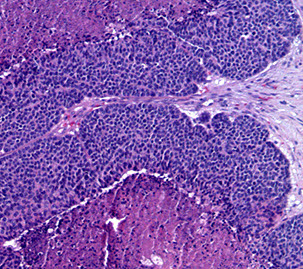

Adenoid Cystic Carcinoma

- aka cylindroma

~1/15 of all salivary gland tumors; seen in older women

- mostly (60%) seen in minor salivary glands, esp in the palate; (MC malignant tumor of minor salivary glands)

Have extensively invasive growth patterns, esp perineural invasion

Micro: Biphasic c ductal lining and ME cells with cribriform, tubular or solid pattern and hyaline material filling the spaces bwt tumors (stromal hyalinization [thick BM])

- usually contains at least some cribriform nests (Swiss cheese) filled c myxoid (blue goo), but may not be present on small bx

- tumor cells should not have intracytoplasmic mucin (found in MEC) - mucin is secreted into pseudocysts - also shound not have squamous metaplasia

- considered high-grade if >30% has solid growth pattern - has calcification / comedonecrosis in high grade

Genes: LOH at 6q23-35, MYB-NFIB in 1/2

IHC: (+) ME pos for CK (lumen epithelial cells) / p63 (basal-myoepithelial cells) / calponin / SMA / S100 / GFAP, epithelium pos for CK/EMA/CEA/c-kit (luminal) and CD117???

DDx: PLGA (PLGA has less mits, less hyperchromasia, less dense fibrous stroma, smaller nests and less nuclear polymorphism); PA

Tx: Radical excision and rads

Px: Tend to recur and met; thus are high risk and have relatively low 5- and 10-year survivals (MC mets to lung)

- high tendency for perineural invasion

Adenoid cystic ca

High grade adenoid cystic ca c comedo necrosis